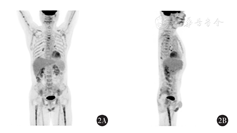

患者于2016年6月20日至10月10日接受6个周期R-CHOP方案治疗,具体为利妥昔单抗686 mg第1天,环磷酰胺1.4 g第2天,盐酸多柔比星92 mg第2天,长春新碱2 mg第2天,泼尼松100 mg第2天至第6天。治疗结束后评估疗效为不确定的完全缓解(CRu)。2017年11月1日疾病进展(PD),2017年12月至2018年3月行ICE方案治疗6个周期,具体为依托泊苷0.17 g第1天至第3天,卡铂0.47 g第2天,异环磷酰胺8.4 g第2天,疗效评估CR。2018年8月PET-CT检查示病情复发,颈、胸、腹、盆部多发淋巴结较前增大,多处氟代脱氧葡萄糖(FDG)代谢增高。后予EPOCH方案治疗4个疗程,最终疗效评估为部分缓解(PR)。因经济情况受限,在获得缓解后,未接受ASCT。2019年7月18日复查颈、胸、腹CT及PET-CT均提示PD。随后参加JWCAR029[CD19靶向嵌合抗原受体T细胞(CAR-T)注射]研究,于2019年8月29日行CAR-T治疗。2019年11月14日PET-CT提示PD(图1)。发病以来,患者一般状况良好,饮食正常,睡眠正常,大小便正常。既往体健,高血压病史3年余。

患者于2019年12月自愿参加pola的同情用药项目,决定给予pola联合利妥昔单抗治疗。治疗前诊断分期为DLBCL,non-GCB型,ⅢA期,美国东部肿瘤协作组(ECOG)评分1分。2019年12月11日给予利妥昔单抗+ pola治疗,利妥昔单抗700 mg静脉滴注第1天,pola 125 mg静脉滴注第2天90 min,每3周重复。第1个疗程利妥昔单抗输注过程中出现了畏寒和发热的首次输注反应症状,对症处理后缓解;pola输注过程顺利。随后进行后续5个疗程相同方案的治疗,至2020年4月10日治疗结束,患者无发热、盗汗、呼吸困难、体质量减轻、呕吐、胸痛或腹痛等不良事件发生。治疗2个疗程复查CT,与2019年11月14日CT检查结果比较,两侧颈血管鞘区、颈后三角、两侧颌下、须下、两侧颈根部、两侧锁骨上、两侧腋窝、纵隔、腹腔及腹膜后、两侧盆壁、腹股沟多发稍大淋巴结,较前明显缩小,中期疗效评价为PR。2020年5月治疗结束后疗效评价示,PET-CT结果与基线比较,原各处病灶淋巴结体积均明显减小,FDG代谢明显减低,且不高于正常值,临床疗效评价为CR(图2)。2020年9月及2021年1月增强CT结果均显示未见复发,至截稿前患者无进展生存时间已超过13个月。